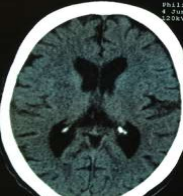

Radiology

Fig 1,2,3,4,5,6,7,8,9,10,11,12,13,14,15

Figure 1

Figure 2

Figure 3

Figure 4

Figure 5

Figure 6

Figure 7

Figure 8

Figure 9

Figure 10

Figure 11

Figure 12

Figure 13

Figure 14

Figure 15